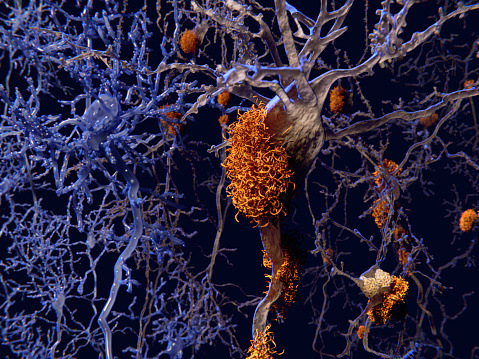

Psoriasis drug may help treat Alzheimer’s disease: Study

Psoriasis drug may help treat Alzheimer’s disease, according to research findings. The number of people living with dementia is expected to grow exponentially by the year 2050, so there is a pressing need for treatment options for dementia and Alzheimer’s disease. Dementia is one of the most common health problems among the elderly. Researchers at ...click here to read more